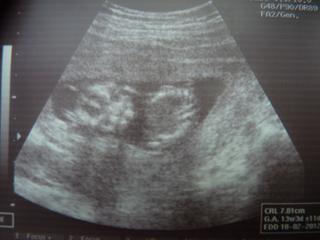

Moje mimi mělo teraz 5,7 cm (po zadeček) - což prý odpovídá 12+2 (a byla jsem podle MS 11+4) Takže je o drobec větší...Ale počítá se velikost dle ultrazvuku - tedy 12+2 týden